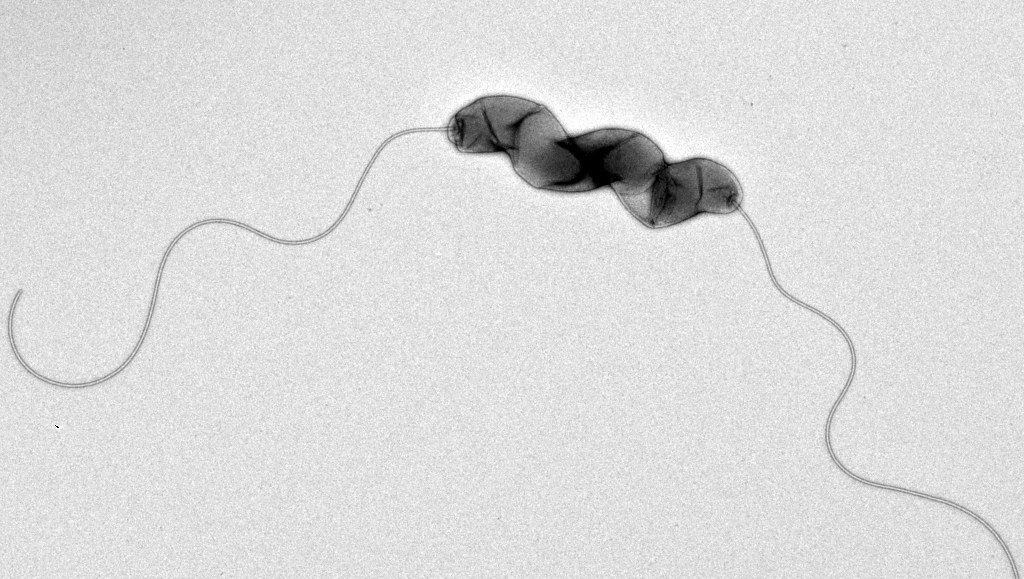

Кампилобактер фетус: патогенез и инфекции